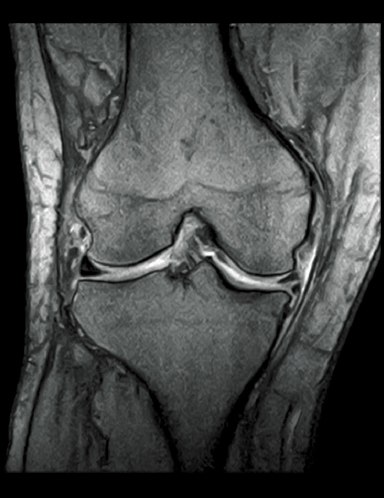

T2WI